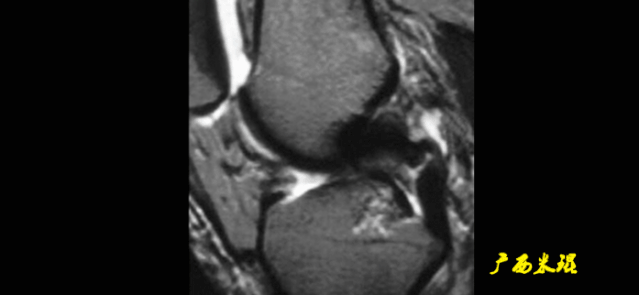

3)方向异常(ACL 下垂征):

-

有较完整的韧带低信号,但方向异常,呈下垂状。

一般见于股骨附着部的陈旧损伤,损伤的ACL下垂并粘附在PCL上。